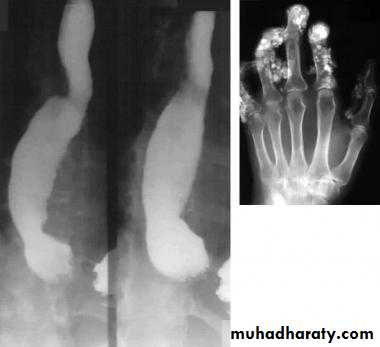

Dilatation

CausesEsophageal atresia

Types:• isolated atresia 8%

• Proximal fistula with distal atresia 1%

• Proximal atresia with distal fistula 85%

• Double fistula with intervening atresia 1%

• Isolated fistula [H-type] 4%